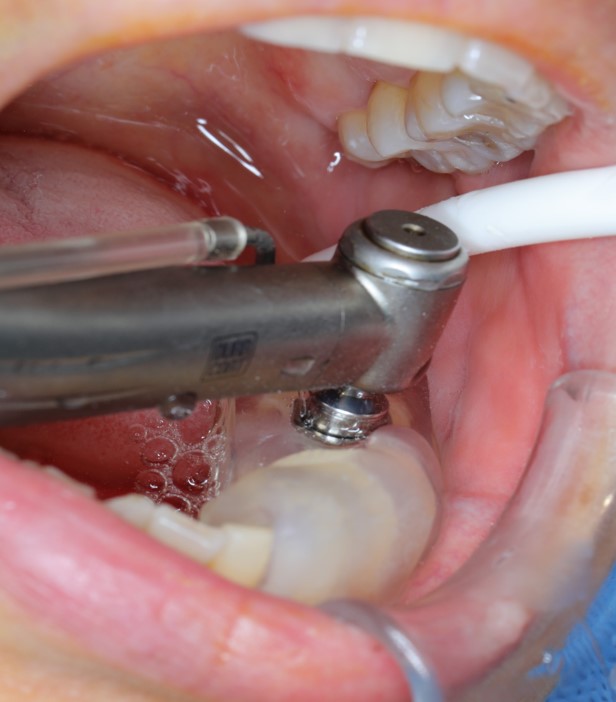

- 手術過程,在植入植體前先用導板定位,確認植牙位置及角度。

- 手術中先使用導板定位,確認植牙角度及位置

- 藉由導板的定位,無須劃開傷口,精準的植入植體。

- 植入植體後不用劃開傷口無須縫合,鎖上癒合帽等待骨整合完成,過程輕鬆舒適。